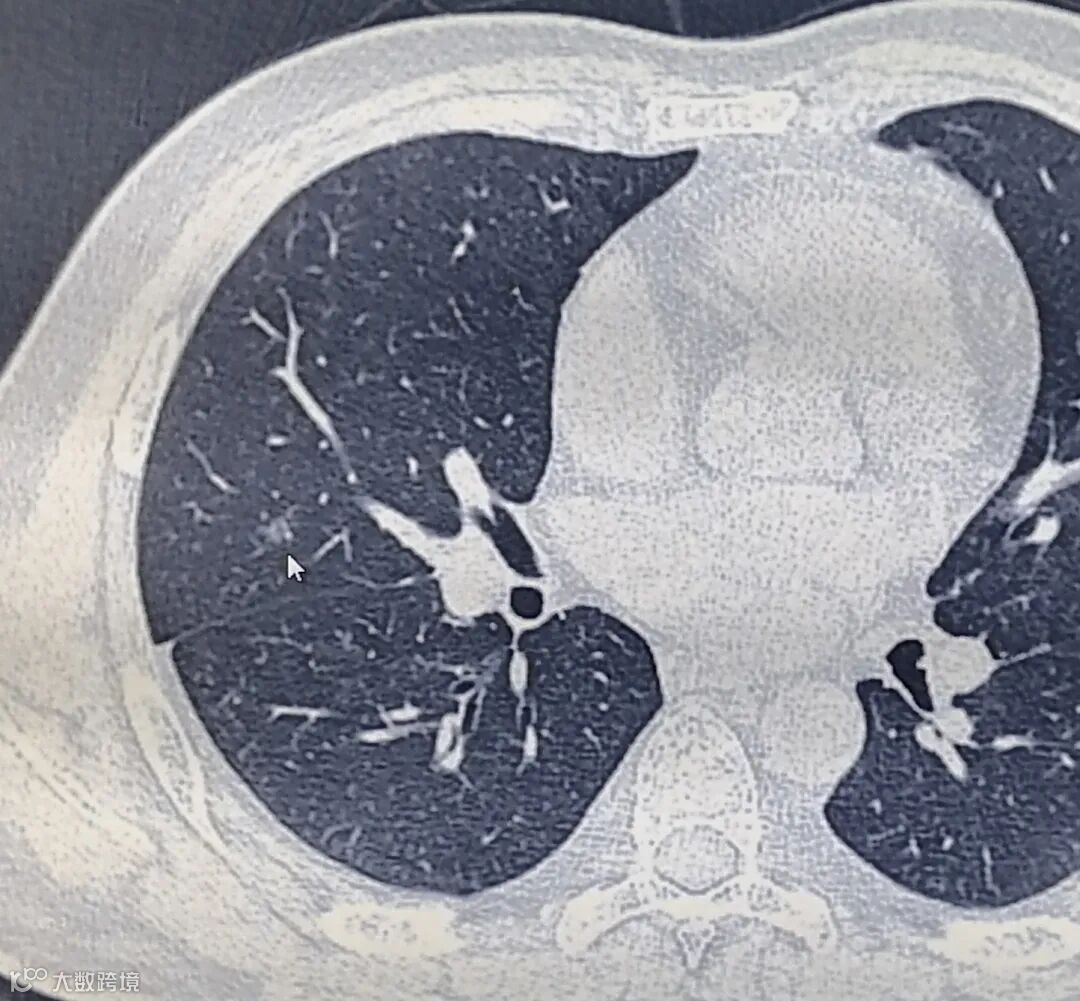

根据肺内小结节的密度可以分三类:

①实性结节

②部分实性结节

③磨玻璃结节

不同密度的肺结节,其恶性率也不同,其中部分实性结节的恶性率最高,其次为磨玻璃结节和实性结节。

磨玻璃结节

实性结节

部分实性结节